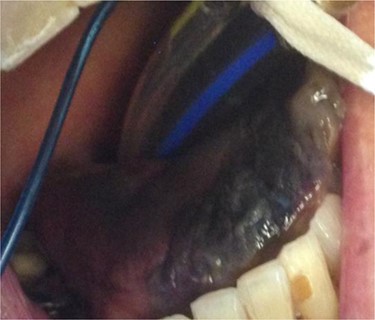

On Day 3, a black tongue was noted, and referral was made to the maxillofacial team (Fig. 1). Blackness of the left tongue dorsum was obvious. The patient was very unwell. Chlorhexidine mouth was prescribed.